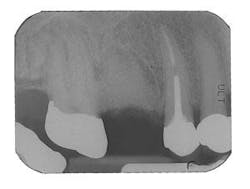

Figure 9 - ITI implant placement Tooth No. 3

Figure 10 - Restored implants

If an extraction is contemplated in an area that will involve future tooth replacement, it is important to consider bone preservation and regeneration at the extraction site. This is necessary to create sufficient bone for a future dental implant, or to preserve esthetics of the ridge if a fixed bridge will be considered. The regenerative capacity of the body is optimal at the time of extraction, so if the site may be thoroughly debrided without concern of leaving residual infection, it is generally best to graft at the time of extraction. The technique involves atraumatically removing the tooth, using a periotome if necessary to preserve as much socket bone as possible. In endodontically treated molars, it is frequently advisable to section the tooth first, so that roots may be removed without trauma and loss of bone. The socket is debrided carefully, removing all tissue tags; a large round bur is used in the socket as an aid in this process. Intramarrow penetration is established and a mixture of Bioglass® material (prepared as previously described) is gently layered into the defect, confirming the presence of blood. Collagen or a connective tissue graft is placed over the graft and the area closed if primary closure is not possible. The area may be protected by a periodontal dressing (if stability may be achieved) or a temporary removable treatment partial (“flipper”). It is important to avoid trauma and pressure over the graft site for several weeks. The site is monitored with a post-bone graft radiograph and again at six to eight months to evaluate the site for a dental implant if that is the intended treatment plan. In most cases, a CT scan is then obtained in order to obtain three-dimensional information on the quantity and quality of bone prior to implant placement.